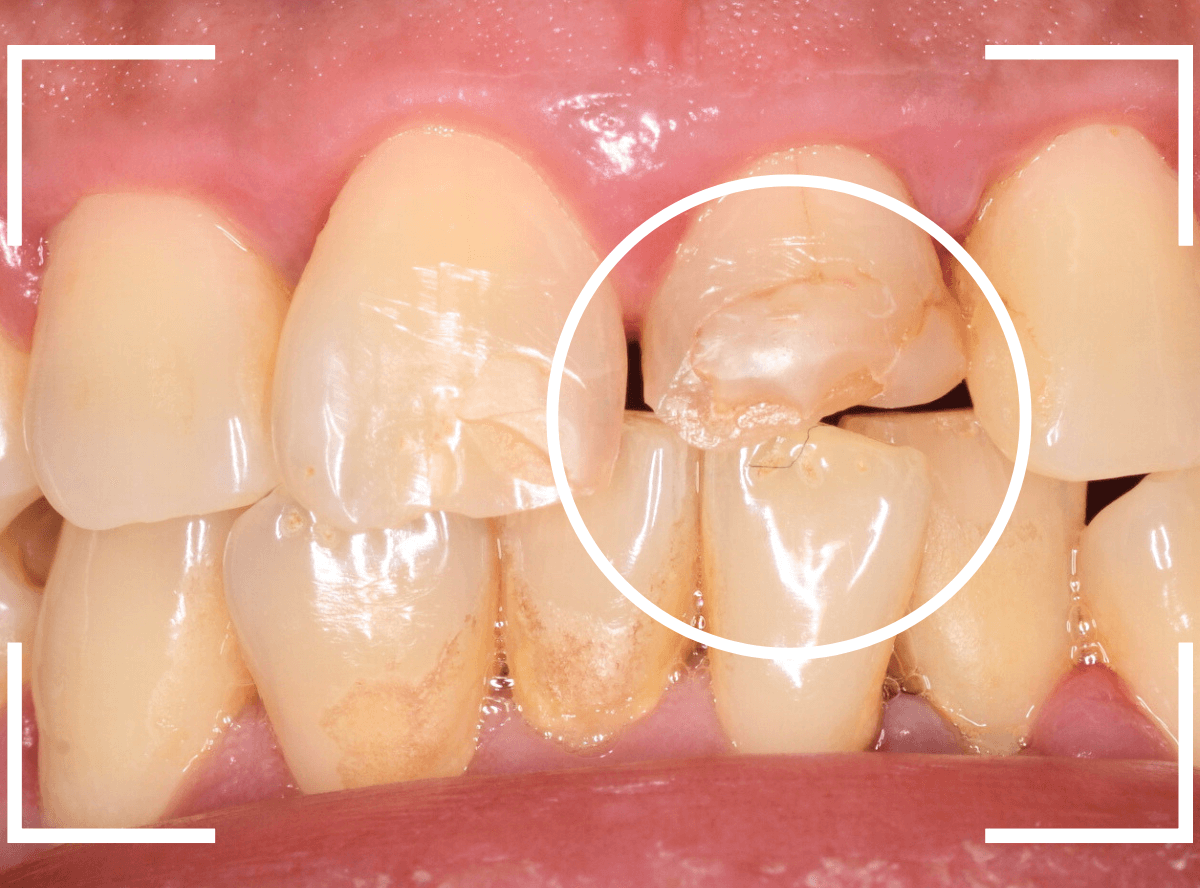

Case.3「前歯がいつも欠けてしまう」というケース

今回は、前歯につめたレジンが、毎回、すぐに欠けてしまうので直してほしいと来院された患者さんのケースです。

お口を閉じてもらうと、下のがレジンをつめたを突き上げて当たってしまうようです。

レントゲン写真上では、歯は問題なさそうでしたが、隣の歯に比べてやけに変色しているので「怪しい」と、歯の神経を調べてみると、神経が死んでいました。

- 歯の神経の治療

- 歯周病の治療

- さし歯(クラウン)の治療

- 下の歯を含めた嚙み合わせの調整

といった治療が必要で、最終修復まで期間がかかる事をご説明の上、同意されました。

まず、歯周病の治療と並行して、神経の治療を行います。

さし歯を被せるために、歯の土台をたてて、歯を削ります。